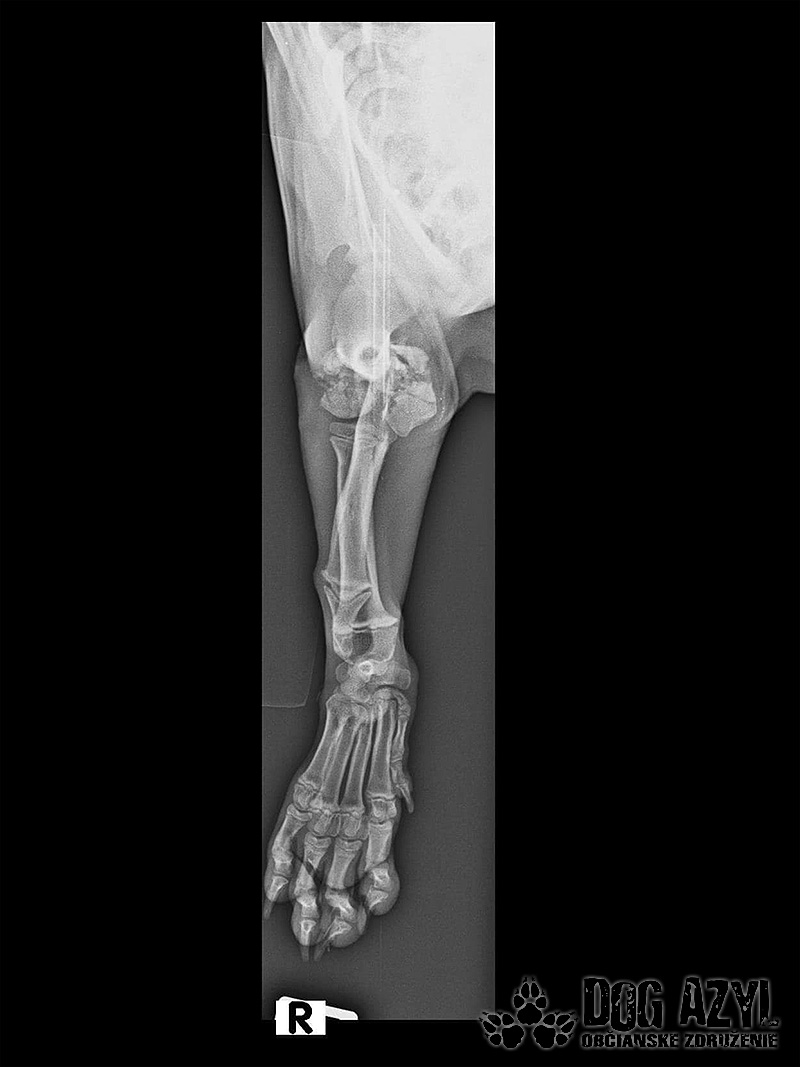

Odoberal sa od drogovo závislých asociálov, ktorý boli vysťahovaný z domu. Ihly, striekačky, ľudské výkaly, rôzne neidentifikovateľné zvratky, špinavé oblečenie, použité kondómy - to všetko nahádzané na jednu kopu v obývačke, kde Pluto so svojou maminkou Miou žili. :( Nevieme ako sa to stalo, kto mu ublížil, ale Pluto má prestrelenú prednú nohu! Viete si predstaviť toho psychicky narušeného človeka, ktorý strieľa na malé bezbranné šteniatko? V dôsledku strelnej rany má doslova rozdrvenú lakťovú kosť. Mali sme veľké obavy, že o nožičku príde, ale MVDr. Vatolík s teamom veterinárnej kliniky Sibra centrum opäť urobil zázrak a malému nožičku napravil a prognóza je viac než dobrá. Čaká ho ešte dlhá cesta k zotaveniu, ale je to odvážny a statočný bojovník. Nechceme si ani len predstaviť čím všetkým si tie zvieratká muesli prejsť, a kto vie koľko ich pôvodne bolo.. Nikto nevie ako a kde skončili Plutovi súrodenci...